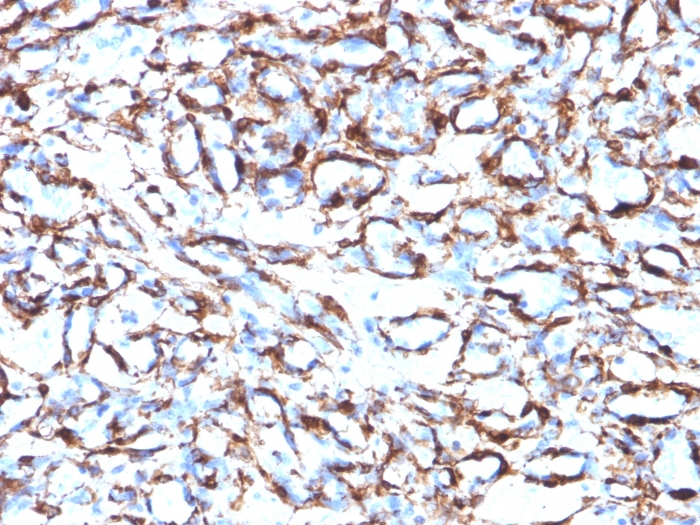

Formalin-fixed, paraffin-embedded human Angiosarcoma stained with Smooth Muscle Actin Monoclonal Antibody (ACTA2/791).